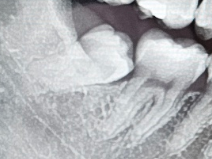

[우측]

• 1번 째 사진

사랑니의 머리가 보인다면 잇몸 절개를 하지 않을 수도 있습니다 하지만 오른쪽 아래에 사장니의 경우에는 발치를 수월하게 하기 위해서 잇몸 절개 후에 진행을 하는 것이 더 좋을 수도 있습니다.

잇몸은 살짝 절개를 하고 치아의 앞부분을 자르고 나서 발치를 해야될것같습니다. 하지만 발치하는과정중에 잘 나오지 않는다면 잇몸뼈 삭제도 해야될수도 잇습니다.

2 케이스 모두 잇몸 절개 및 일부 치조골 삭제가 동반될 가능성이 높습니다. 특히 오른쪽 치아는 치아 절개 및 치조골 삭제가 들어갈 가능성이 크며, 왼쪽 케이스도 뒤쪽 부위가 뼈에 걸려 있다면 해당 부위의 치조골 삭제가 필요합니다.